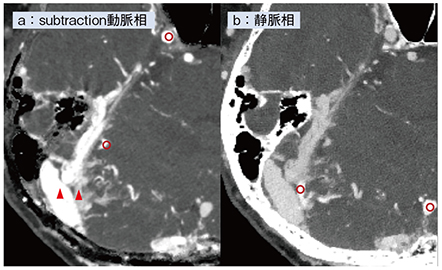

症例4は,medial側とlateral側のテント部にシャントのあるdAVFの症例である。図5はPCD-CTの画像であるが,サブトラクション動脈相の画像では,動脈のCT値と,逆流している静脈のCT値はほぼ一致している(図5 a○)。一方,静脈相の画像では,順行性に還流する皮質静脈と,本来正常な還流静脈のCT値は一致するのに対し,病変部の静脈もしくはシャント部位のCT値は低下している(図5 b○)。この差を利用することで,正常に還流する静脈と逆流している静脈を見分けることが可能となる。シャント部位近傍の静脈は逆流している可能性があるが,動脈相の画像(図5 a)ではCT値は高くなく(▲:右側),逆に静脈相の画像(図5 b)ではシャント部位よりCT値は高く(○:左側),正常還流であることがわかる。

図5 症例4:PCD-CTによるテント部dAVFの静脈の評価